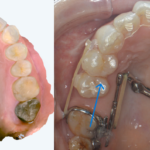

歯は、歯ぐきや歯槽骨(歯を支える骨)という土台の上に立っています。

治療前の検査で、

- 歯ぐきが薄い

- 歯槽骨が少ない

と分かることがあります。

こうした場合、見た目を整えることだけを優先すると、

治療後の安定性に影響が出る可能性があります。